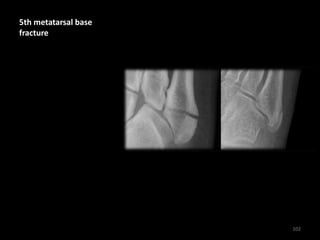

5th metatarsal base

fracture

102

• Left image - The

fracture line passes

transversely across the

bone

• Right image - A normal

unfused 5th metatarsal

base apophysis is

aligned more

longitudinally along

the bone

103